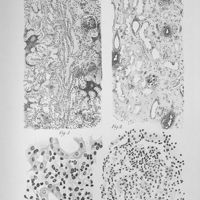

![0077 - Pl. IV - [Planches]](https://numerabilis.u-paris.fr/iiif/2/bibnum:110133x145x07:0077/square/200,/0/default.jpg) 0077 - Pl. IV - [Planches] 0077 - Pl. IV - [Planches]